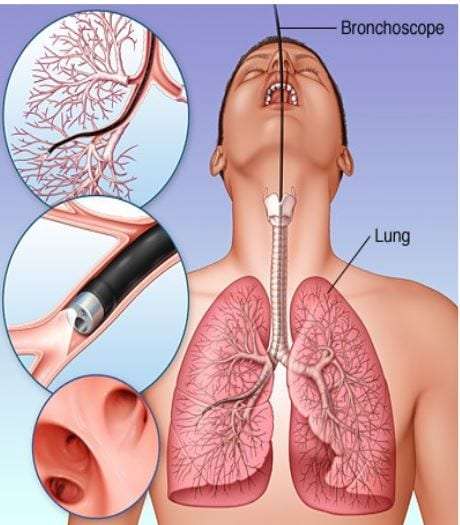

Фотографии заболеваний бронхолегочной системы